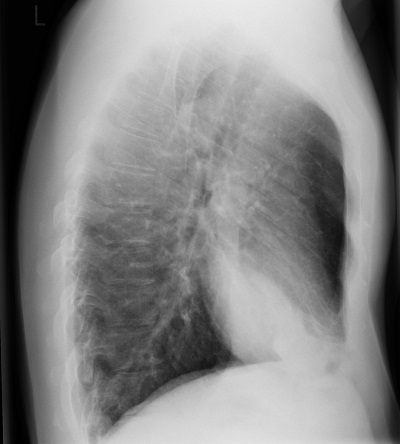

- Gold Standard: PA and Lateral Chest X-ray

Lobar consolidations (focal area of solidified tissue) can be found as a reaction to local infections. Interstitial infiltrates, which is the connective space between alveoli visible due to invasion of fluids, occur in pneumonia as an inflammatory response to infection. Cavitating lesions occur in some diseases such as tuberculosis, where gas-filled space develops with thick walls around it.